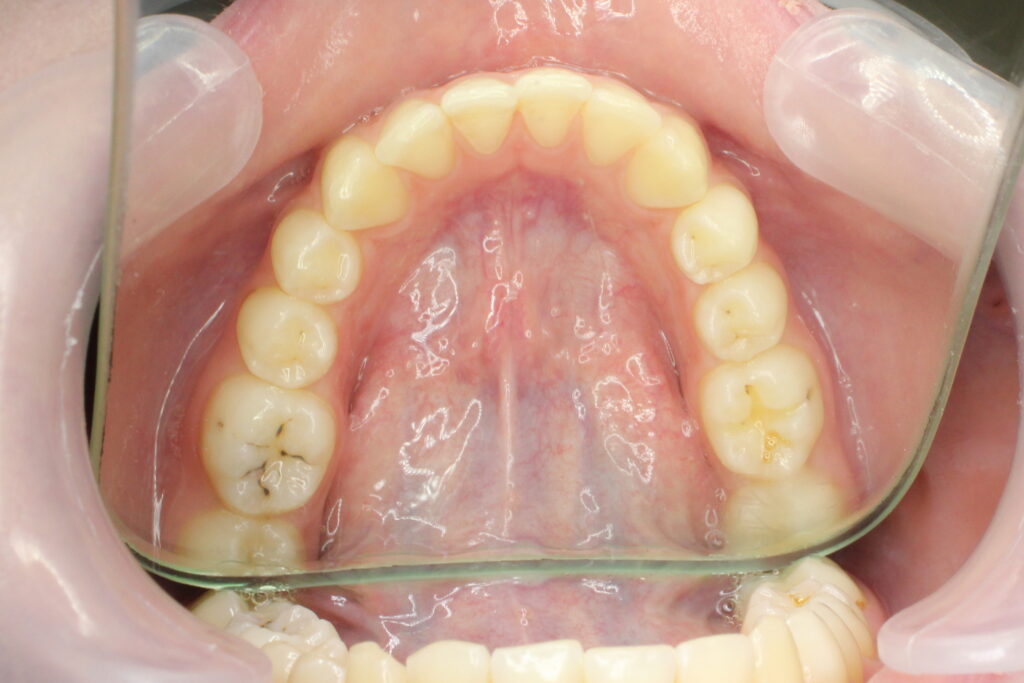

Результаты

результат лечения брекет-системой